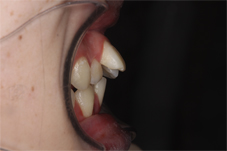

笑った時の八重歯を気にして来院された患者さまです。

写:矯正治療前、右:治療後

上下とも八重歯の状態が治療後は改善しています。歯並びがきれいに並んで、その後ホワイトニングも行いました。

前歯の歯並びのでこぼこも解消しました。

上の前歯が前に突出していた状態も改善して前歯が引っこんでいます。

前歯の歯並びが改善すると笑った時の雰囲気もかなり変わりますよね。この後すぐに結婚式が控えておりましたが、ホワイトニングも行って挙式に臨んでいただきました。